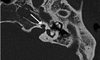

- Qual o nome dessa malformação óssea? - Qual achado deve ser considerado para diagnóstico dessa anomalia? - Qual o quadro clínico? - Quais síndromes estão associadas? - Qual o tratamento indicado?

- Síndrome do Aqueduto Vestibular Alargado (SAVA). - Acima de 1,5 mm (ou 2mm) de diâmetro na sua porção média OU maior do que o diâmetro do CSC Posterior (na TC é opontinho que fica superior e lateral ao aqueduto). - Quase sempre o problema é bilateral e simétrico. PANS ou PAM, progressiva ou súbita, flutuante ou contínua, congênita ou precoce na criança ou tardia no adulto. (clássico = criança com PANS progressiva flutuante). Toda perda mista em criançam investigar SAVA. Não existe relação entre a perda auditiva e grau de alargamento - Mondini, Pendred, Swartze, Braquio-otorrenal e surdez ligada ao X. - AASI OU IMPLANTE COCLEAR (tratamentos cirúrgicos foram abandonados, não sendo mais realizados).